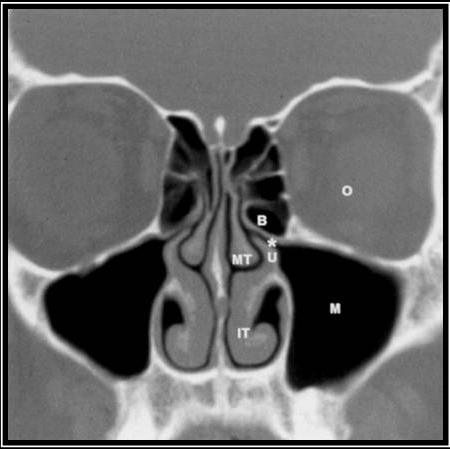

CT sinuses

Ordered if complications are suspected, or if further investigation is required (e.g., with recurrent episodes, suspected anatomical abnormalities) to rule out alternative diagnoses. Not recommended for evaluation of routine, uncomplicated acute rhinosinusitis.[1]

CT scan with contrast is the imaging study of choice for acute rhinosinusitis with suspected complications.[1][24] Sinus opacification, air-fluid level, or marked or severe mucosal thickening is consistent with, but not diagnostic of, acute rhinosinusitis.[1] A completely normal scan excludes the diagnosis of rhinosinusitis.

CT without contrast may be appropriate if invasive fungal rhinosinusitis is suspected or for bony evaluation and surgical planning, but it is not as useful as a contrast CT for detecting orbital and intracranial complications.[24]

CT cannot differentiate acute viral from acute bacterial rhinosinusitis, so clinical diagnosis is essential.[15][24]

[Figure caption and citation for the preceding image starts]: Normal non-contrast computed tomography scan of the sinusesFrom the collection of Melissa Pynnonen, MD [Citation ends].

identifies extent of sinus disease, abnormal anatomical structures